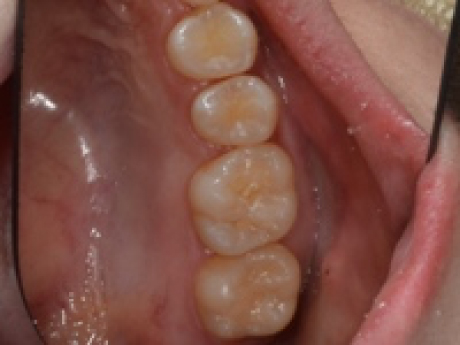

case2